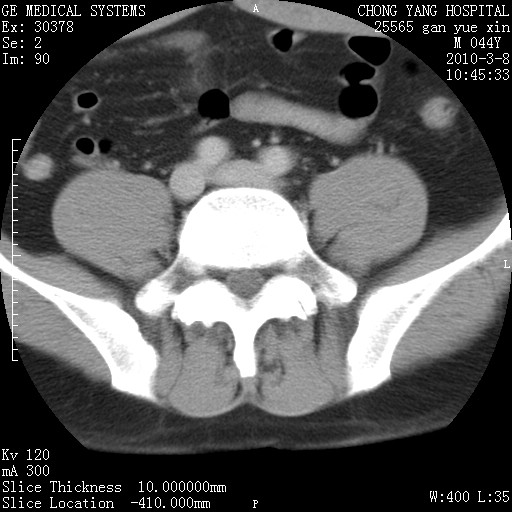

标题: CT24940:主动脉增强,典型病例。 [打印本页]

标题: CT24940:主动脉增强,典型病例。

夹层动脉瘤。

动脉夹层

夹层动脉瘤,典型

主动脉夹层。

动脉夹层的分型:

⒈debakey分型:根据主动脉夹层累及部位,分为三型:ⅰ型:原发破口位于升主动脉或主动脉弓部,夹层累及升主动脉、主动脉弓部、胸主动脉、腹主动脉大部或全部,少数可累及髂动脉。ⅱ型:原发破口位于升主动脉,夹层累及升主动脉,少数可累及部分主动脉弓。ⅲ型:原发破口位于左锁骨下动脉开口远端,根据夹层累及范围又分为ⅲa,ⅲb。ⅲa型:夹层累及胸主动脉。ⅲb型:夹层累及升主动脉、腹主动脉大部或全部。少数可累及髂动脉。

⒉stanford分型:a型:夹层累及升主动脉,无论远端范围如何。b型:夹层累及左锁骨下动脉开口以远的降主动脉。

夹层动脉瘤,少量胸水

夹层动脉瘤;左侧少量胸腔积液。

典型主动脉夹层。